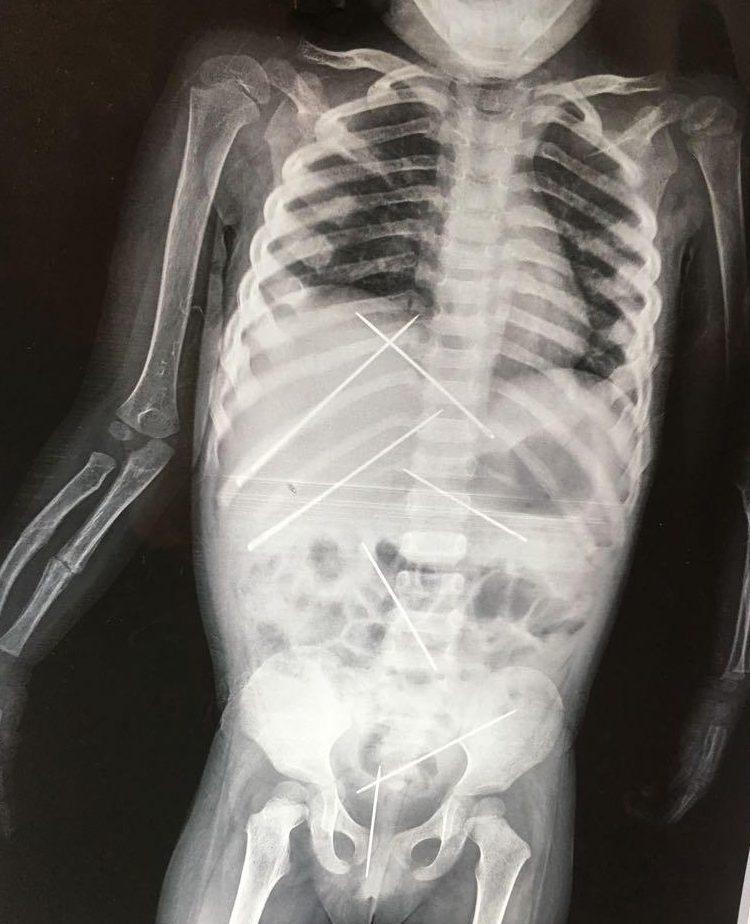

Όταν υποβλήθηκε σε ακτινογραφία, οι γιατροί αντίκρισαν ένα πρωτοφανές θέαμα. Σχεδόν 10 μεγάλες βελόνες είχαν καρφωθεί μέσα στο σώμα του 3χρονου κοριτσιού, σε διάφορα σημεία. Επίσης, το ένα χέρι του παιδιού ήταν σπασμένο.

Το 3χρονο κορίτσι υποβλήθηκε σε εγχείρηση και της αφαιρέθηκαν οι βελόνες μέσα από το σώμα της.